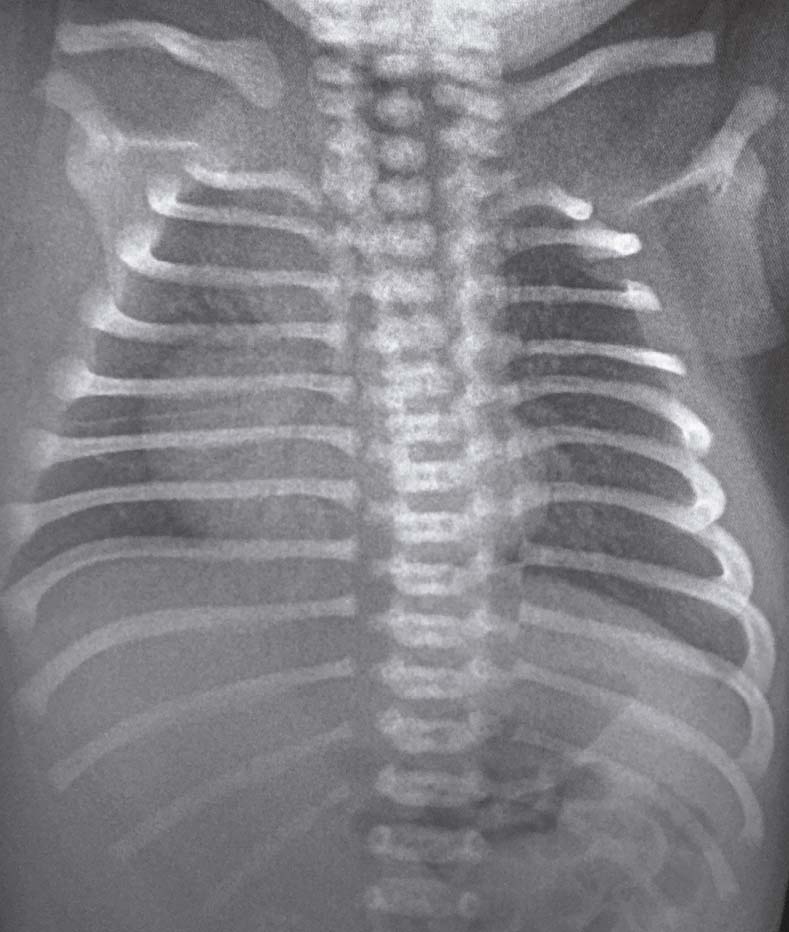

<body><![CDATA[<p align="justify"><font size="2" face="Verdana, Arial, Helvetica, sans-serif">Dicho movimiento era   compatible con una respiraci&oacute;n parad&oacute;jica, por lo que se sospecha de fracturas   m&uacute;ltiples de costillas secundarias a probable trauma durante la ces&aacute;rea. </font></p>     <p align="justify"><font size="2" face="Verdana, Arial, Helvetica, sans-serif">La saturaci&oacute;n de oxigeno   era del 92% a los 5 minutos de vida, APGAR 9 al minuto y a los 5 minutos.   Auscultaci&oacute;n pulmonar y cardiaca sin anormalidades. Se evidencia cianosis acral   propia del reci&eacute;n nacido. La inspecci&oacute;n del hemit&oacute;rax izquierdo evidencia una   disminuci&oacute;n del tejido subcut&aacute;neo, masa muscular e hipoplasia del pez&oacute;n (Figura   2). </font></p>     <p align="center"><img src="/img/revistas/gmb/v41n1/a13_figura2.jpg" width="378" height="252"></p>     <p align="center">&nbsp;</p>     <p align="center"><font size="2" face="Verdana, Arial, Helvetica, sans-serif">Figura 2. T&oacute;rax del reci&eacute;n nacido donde se muestra la hipoplasia del pez&oacute;n y asimetr&iacute;a del t&oacute;rax</font>.</p>     <p align="justify"><font size="2" face="Verdana, Arial, Helvetica, sans-serif">Resto del examen f&iacute;sico sin hallazgos patol&oacute;gicos. </font><font size="2" face="Verdana, Arial, Helvetica, sans-serif">Se indica inmediatamente   radiograf&iacute;as de t&oacute;rax en sala de partos para descartar fracturas o patolog&iacute;a   pulmonar. Las radiograf&iacute;as no constatan presencia de fracturas de costillas ni   patolog&iacute;a en par&eacute;nquima pulmonar. Silueta cardiaca normal, pero en situaci&oacute;n   derecha, compatible con dextrocardia, hallazgo generalmente asociado a la ausencia del pectoral del lado izquierdo como en nuestro caso (Figura 3).</font></p>     <p align="center">&nbsp;</p>     <p align="center"><img src="/img/revistas/gmb/v41n1/a13_figura3.jpg" width="370" height="436"></p>     <p align="center"><font size="2" face="Verdana, Arial, Helvetica, sans-serif">Figura 3. Rayos X de t&oacute;rax AP donde se muestra la dextrocardia. Estructuras Oseas dentro de par&aacute;metros normales.</font></p>     <p align="justify"><font size="2" face="Verdana, Arial, Helvetica, sans-serif">Radiograf&iacute;a abdominal   dentro de par&aacute;metros normales. Se realizan hemograma, PCR, sin demostrar   anormalidades. </font><font size="2" face="Verdana, Arial, Helvetica, sans-serif">Por las caracter&iacute;sticas   cl&iacute;nicas se sospecha S&iacute;ndrome de Poland. Se realiza ecograf&iacute;a de pared   tor&aacute;cica, la cual indica adelgazamiento del tejido muscular y subcut&aacute;neo de   hemit&oacute;rax derecho lo cual confirma el diagn&oacute;stico. No se realiza ecograf&iacute;a   abdominal. </font></p>     ]]></body>